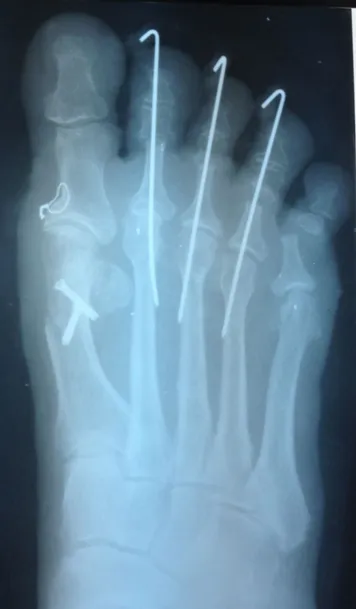

After Surgery

After Correctional Foot Surgery X-Ray